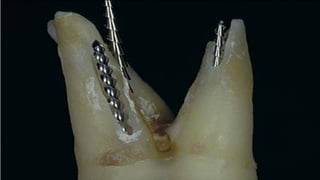

It contains pulp or pulpally derived tissue and acts as store house for bacteria

Types

Type•I

Incomplete isthmus; faint

communication between two

canals.

Type• II

Characterized by two canals with

definite connection between

them.

Type• III

Very short complete isthmus

between two canals.

Types. IV

Complete or incomplete isthmus

between two or more canals.

Type. V

Marked by two or three canal

openings without visibleconnections